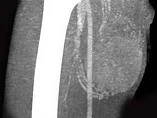

- 单项选择题男,30岁, 主诉右大腿肿块年余,逐渐增大, 局部胀痛及压痛,根据图像表现, 最可能的诊断是 ( )

D、横纹肌肉瘤